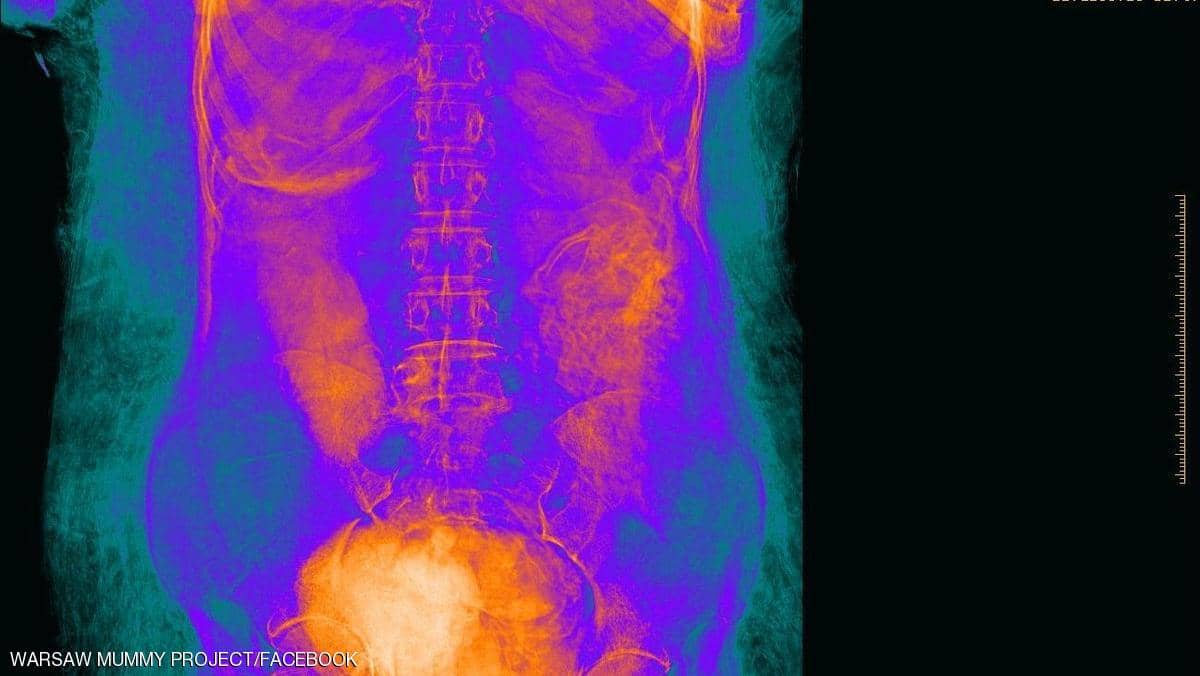

6-تم إخضاع المومياء لعدة مجموعات من التصوير المقطعي والأشعة السينية وتصور ثلاثي الأبعاد مما سمح بفحص دقيق للجنين بأكمله والذي أثبت أن المرأة كانت في الأسبوع 26-28 من الحمل

ولسوء الحظ تم الكشف عن القليل جدا عن الطفل المحنط ويقترح الخبراء أن الطفل كان ملفوفا في وضع الجنين 👇